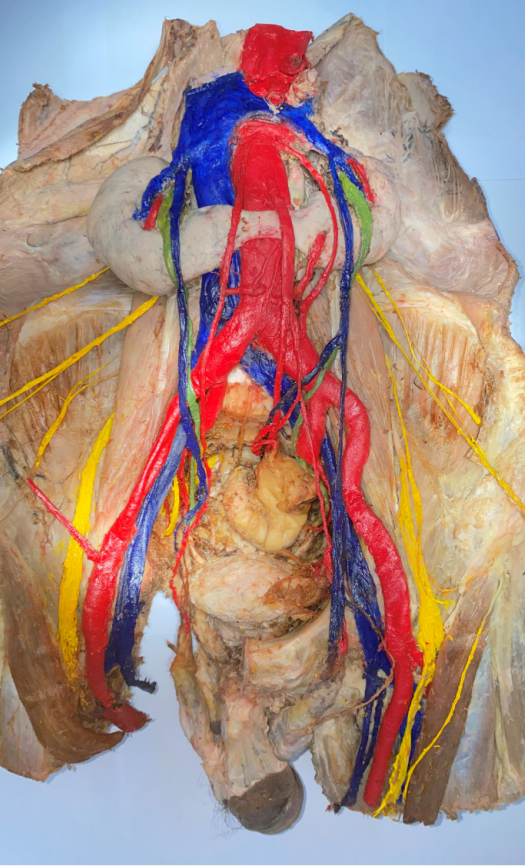

马文琪《肠系膜上动静脉的供血》

《两肾相连囊肿生,腹有斑斓隙自华》

《腹中有乾坤,吐纳“肠”自在》